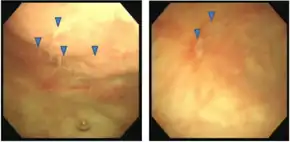

Hunner ulcer seen in interstitial cystitis by cystoscopy[3][4] | |

During cystoscopy, 5–10% of people with IC are found to have Hunner's ulcers.[11] A person with IC may have discomfort only in the urethra, while another might struggle with pain in the entire pelvis. Interstitial cystitis symptoms usually fall into one of two patterns: significant suprapubic pain with little frequency or a lesser amount of suprapubic pain but with increased urinary frequency.[12]